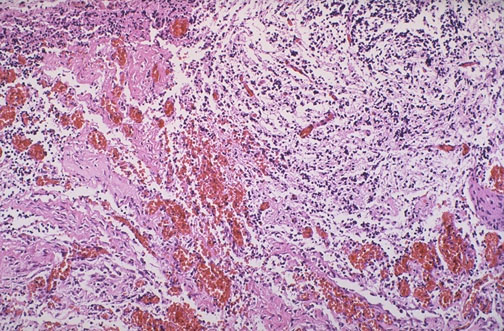

Microscopically, the "area cerebrovasculosa" from the base of the skull from an anencephalic consists of scattered primitive neuroglial tissue elements within an irregular vascular proliferation.